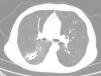

Our patient was a 70-year-old man, with a history of active smoking, diabetes mellitus, ischemic heart disease, and CD. He was admitted in June 2016 with a 2-day history of hemoptysis. Chest radiograph revealed an opacity in the right lower lobe (RLL). The chest computed tomography (CT) revealed a poorly defined pseudonodular cavitary lesion, measuring 35mm in its longest diameter, in an upper segment of the RLL, and multiple adjacent centrilobular and ground glass opacities (Fig. 1). No diagnosis was reached with either fiberoptic bronchoscopy or CT-guided needle biopsy of the lesion, so a PET-CT was performed, showing significant pathological uptake. An intraoperative biopsy was then performed, and the pathology study reported a diagnosis consistent with a chronic inflammatory necrotizing granulomatous process, probably due to TB. Unfortunately, the sample was not submitted for microbiological study, and the patient was diagnosed with probable TB.